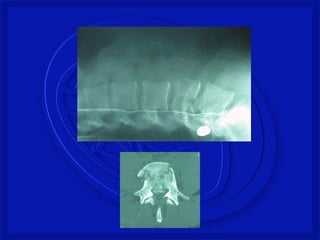

As lesões ocorrem por:

-Flexão, extensão, rotação, compressão

por impacto axial ou combinação desses

mecanismos.

Mecanismo de Trauma Raqui-

Medular com fratura

FRATURA COMPRESSÃO TORÁCICA

BAIXA